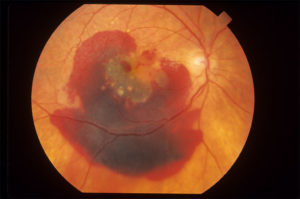

4.Retinal blood vessel blockage diseases.

What is retinal vascular blockage?

Retinal blood vessel occlusion affects the eye, specifically the retina. The retina is the light-sensitive layer of tissue that lines the back of your eye. It’s covered with special cells called rods and cones that convert light into neural signals and send these signals on to the brain so you can see. The retina is vital for vision.

The vascular system includes blood vessels called arteries and veins, which transport blood throughout your body, including your eyes. Your retina requires a constant supply of blood to make sure your cells get enough nutrients and oxygen. Blood also removes the waste your retina produces. However, it’s possible for one of the vessels carrying blood to or from the retina to become blocked or to have a blood clot. This is called an occlusion.

The occlusion can cause blood or other fluids to build up and prevent the retina from properly filtering light. When light is blocked or fluids are present, a sudden loss of vision can occur. The severity of vision loss may depend on where the blockage or clot occurred.

Retinal vascular occlusion is a potentially serious condition, especially if hardening of the arteries, or atherosclerosis, already exists. It most often occurs in middle-aged and older people.

CRVO

BRVO

CRAO

What are the different types of retinal vascular occlusion? [see photos above]

There are two types of retinal vascular occlusion. The type depends on which blood vessel is affected:

1.Retinal vein occlusion

Retinal vein occlusion is blockage of one of your retinal veins, which are blood vessels that carry deoxygenated blood back to your heart. Retinal vein occlusion is also divided into two types:

- Central retinal vein occlusion (CRVO) is a blockage in the main vein of your retina, which is called the central retinal vein.

- Branch retinal vein occlusion (BRVO) occurs when the blockage is in a smaller branch of veins throughout the retina.

2.Retinal artery occlusion CRAO

Retinal artery occlusion is a blockage of one of the retinal arteries, which are blood vessels that carry oxygenated blood from the heart to your retina. A blockage in the main artery of your retina is called a central retinal artery occlusion. A branch retinal artery occlusion happens when the blockage occurs further along in the smaller branches of your artery.

Blockages in your main vein or artery are often more serious than blockages in your branch veins or arteries.

commonest causes are blood pressure,diabetes,high cholesterol,blood clots

Treatment; anti VEGF injections in eye,laser photocoagulation[ varies from case to case]